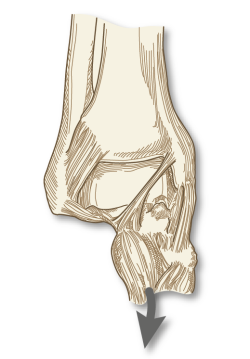

1. El complejo ligamentoso lateral, que se compone, a su vez, del ligamento peroneo-astragalino anterior (LPAA), el ligamento peroneo-calcáneo (LPC) y el ligamento peroneo-astragalino posterior (LPAP). El LPAA se origina en el aspecto anterior del peroné distal y se inserta en el cuerpo talar justo delante de su faceta articular, siendo confluente con la cápsula lateral (Figura 1). El LPC se origina distalmente al origen del LPAA y se inserta en el calcáneo (Figura 1). El LPAP se origina en el aspecto posteromedial del maléolo lateral y tiene una amplia inserción en la zona posterior del calcáneo(2)(Figura 2).

Figura 2. Visión posterior de una disección osteoarticular del tobillo y la articulación subtalar. 1: os trigonum; 2: ligamento calcaneofibular; 3: ligamento talofibular posterior; 4: ligamento intermaleolar; 5: componente profundo del ligamento tibiofibular posterior (ligamento transverso); 6: componente superficial del ligamento tibiofibular posterior; 7: surco para el tendón del tibial posterior; 8: parte posterior del ligamento deltoideo; 9: rotura de la sincondrosis entre un os trigonum y el cuerpo del astrágalo; 10: túnel osteofibroso para el flexor largo del primer dedo. Figura cedida por el Dr. Miki Dalmau-Pastor, publicada en “Anatomía del tobillo” en este mismo monográfico.